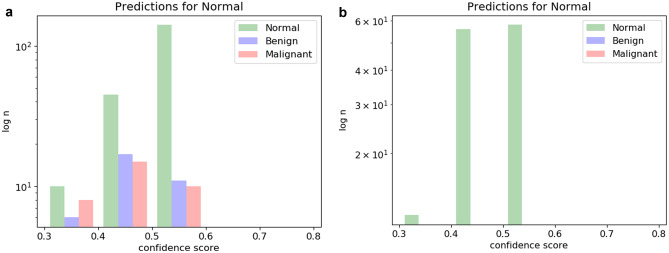

With respect to the goal of using the mammogram classifier cascade to identify normal studies with high confidence and either discard them from further evaluation (or triage them for later review), Fig. 3 demonstrates histograms of test cases predicted to be normal and their ground truth. As can be seen in Fig. 3a, the balanced classifier makes many high-confidence false-positive normal predictions, with several malignant images incorrectly classified as normal. On the other hand, the malignancy-weighted classifier is more conservative, making fewer overall predictions for normal, but with 100% accuracy, accounting for 53% of the normal images (Fig. 3b).

Fig. 3.

Histograms of normal prediction studies with ground truth. a Balanced classifier results in many high-probability false positive predictions for normal cases, including several cancers. b Malignancy-weighted classifier makes fewer predictions for normal, but with 100% accuracy